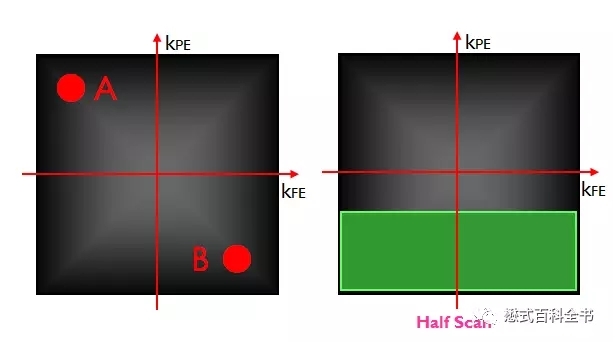

利用K空间的对称性,我们可以做什么呢?当然是加速扫描了。因为,传统来说,我们要重建磁共振图像,得把K空间数据填满,特别是相位编码方向(因为相位编码步级决定扫描时间);如果我们只填充一半相位编码线,这样的话,扫描时间就节约了,在利用K空间的共轭对称性,利用数学算法,算出K空间的另外一半,这样也可以重建图像。

图11:利用K空间对称性,做快速扫描

理论上,在相位编码方向(Ky),由于K空间相位编码方向的对称性,我们只需要填充一半的相位编码线,就可以利用数学算出另外一半,然后重建图像节约扫描时间。这种只填充K空间一半(一半以上)的相位编码线的方法叫做半扫描(部分K空间技术)。

飞利浦中,半扫描叫做Half Scan;

GE公司中,半扫描是怎么做的呢?把NEX(信号激励次数)采用小于1的就可以了;

西门子公司中,半扫描叫做部分傅里叶技术,Phase Partial Fourier。